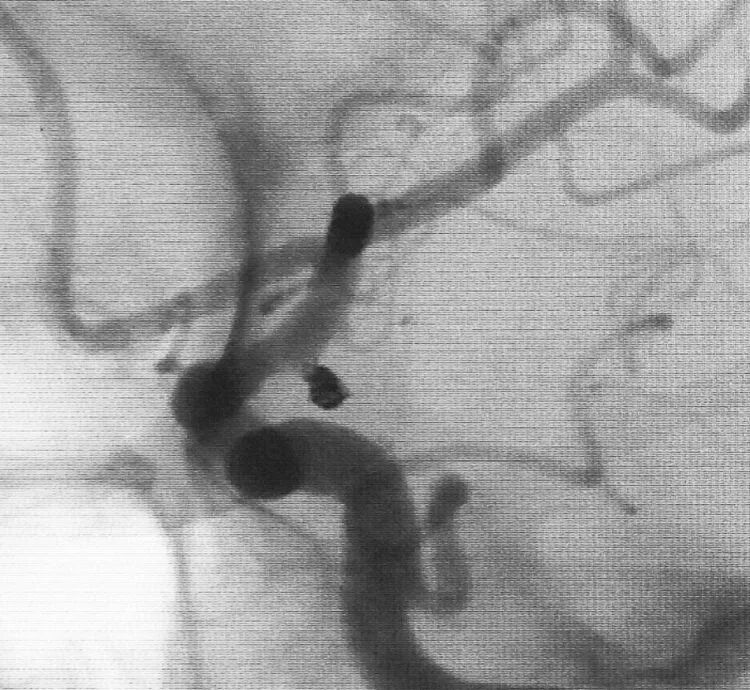

基底动脉顶端微小动脉瘤,是个有欺骗性的病例。从下面这个角度的造影看,瘤体长轴跟基底动脉主干平行,似乎用直头微导管栓塞即可

但从侧位造影和CTA观察,其实瘤体长轴还是跟基底动脉主干有成角的。这家医院的DSA机器没有三维重建工作站,只能参考CTA

于是我们把微导管头塑成S形

顺利完成该动脉瘤的栓塞。所以,要多角度观察动脉瘤跟载瘤动脉的解剖走行,即使硬件上没有三维工作站,咱们头脑中也要有立体构象,不要一叶障目,被狡猾的敌人所欺骗